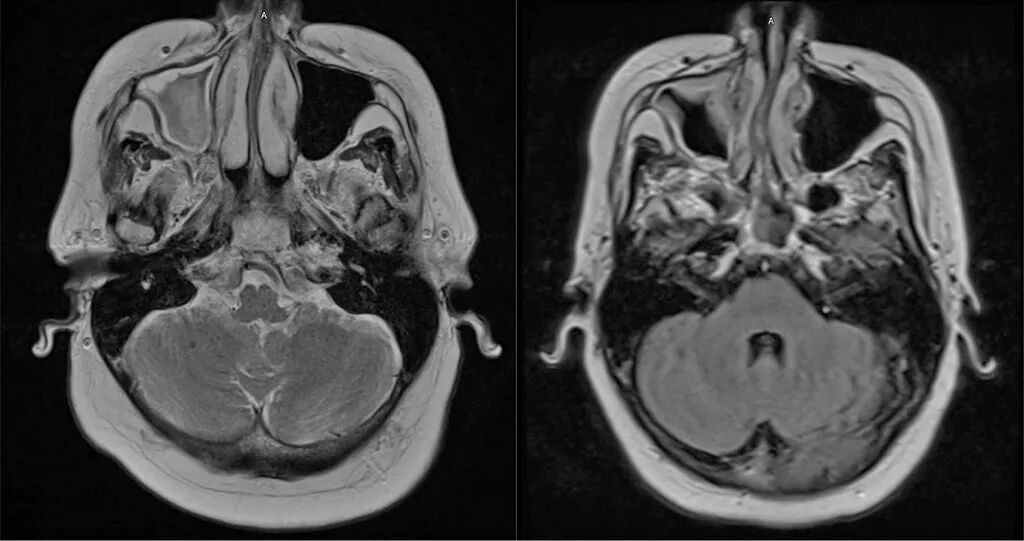

实验室检查显示:C反应蛋白升高(22.5 mg/L),红细胞沉降率正常(19 mm/h),血红蛋白轻度降低(11.6 g/dL),综合代谢指标均在正常范围内。脑部磁共振成像显示右侧上颌窦病变(图1)。

由于药物治疗未能缓解症状,患者接受了鼻窦手术;术后影像学检查证实病变改善(图1)。尽管如此,头痛仍然存在。

图1.左图:鼻窦手术前脑部磁共振成像显示副鼻窦疾病,以右侧上颌窦最为明显。右图:术后磁共振成像显示黏膜增厚有所改善。患者头痛症状未见变化。